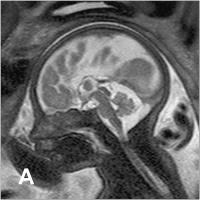

Fetus - Sagittale Schichtführung

Abbildung 1: Sagittale Schichtführung durch einen Fetus in der 27. SSW. Durch das große "Field of View" kann der ganze Fetus abgebildet werden. Das Profil, einschließlich des harten und weichen Gaumens, ist beurteilbar. Intrazerebral erkennt man kortikal den Beginn der Formation der Zentralregion, Hirnstamm und Kleinhirn. Die räumliche Auflösung ist groß genug, um kleine Strukturen wie das Chiasma opticum darzustellen. Intrauterin zeigt sich darüber hinaus eine regelrechte Nabelschnur, die – im Querschnitt getroffen – 3 Gefäße aufweist.